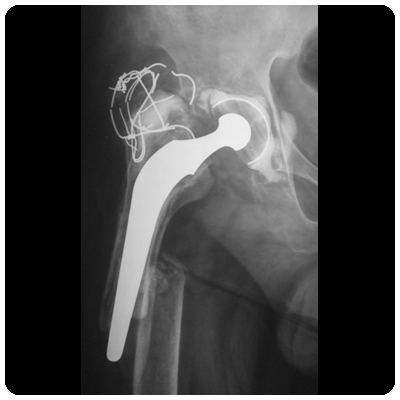

| Pre-Operation | Post-Operation |

![]() Loose Acetabulum with Migration into the pelvis (clickimage for enlarge view) | ![]() Revision Total Hip using allografts and cage in the acetabulum (clickimage for enlarge view) |